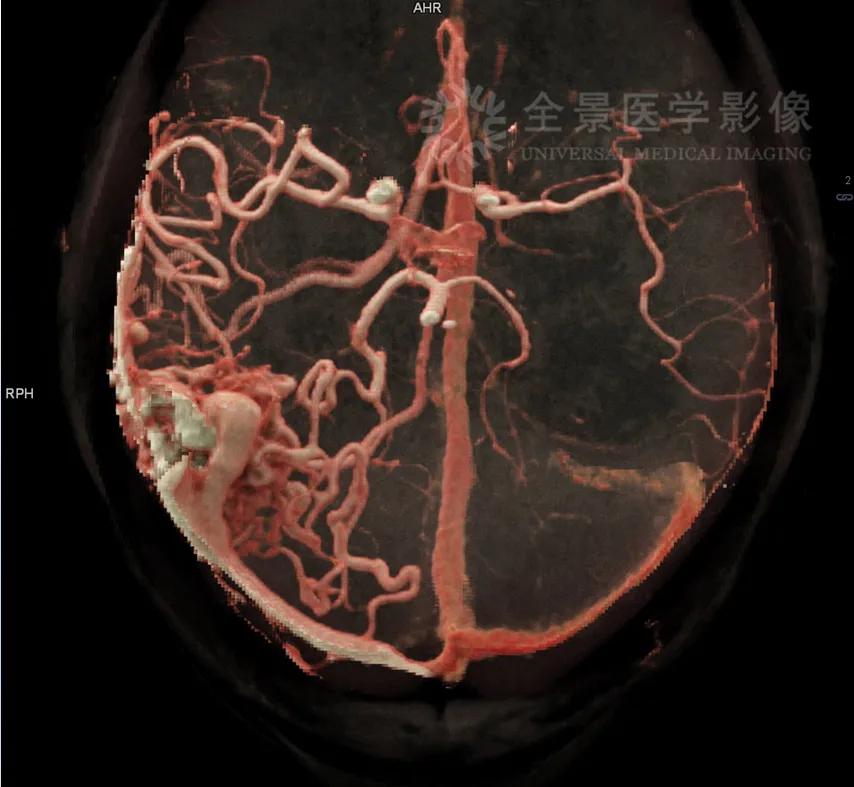

3. 能够清晰地显示血管与周围组织的关系,更加全面地了解血管畸形、外伤累及等情况;

案例:脑血管畸形介入术后5年复查

头颅CTA检查MIP及cVRT重建显示右侧颞枕叶AVM,供血动脉为右侧大脑中、大脑后动脉,引流入右侧横窦、乙状窦。(备注:此案例图片感谢广州中心李创峰医生提供)